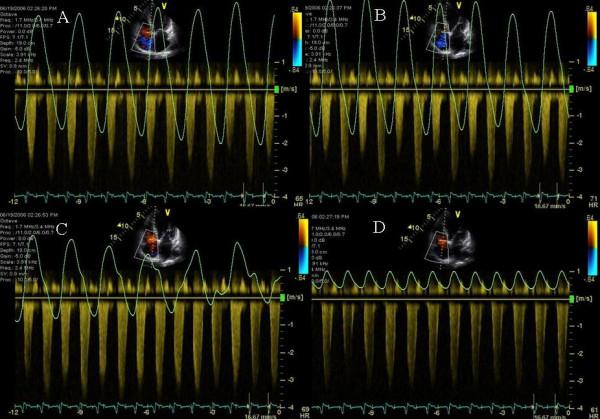

In this report we describe novel therapeutic uses of echo pulsed wave Doppler in atrioventricular pacemaker optimization in patients who had either not derived significant symptomatic benefit post biventricular pacemaker implantation or deteriorated after deriving initial benefit. In these patients atrioventricular optimization showed novel findings and improved cardiac output and symptoms.

In 3 patients with Cheyne Stokes pattern of respiration echo Doppler showed worsening of mitral regurgitation during hyperpneac phase in one patient, marked E and A fusion in another patient and exaggerated ventricular interdependence in a third patient thus highlighting mechanisms of adverse effects of Cheyne Stokes respiration in patients with heart failure. All 3 patients required a very short atrioventricular delay programming for best cardiac output. In one patient with recurrent congestive heart failure post cardiac resynchronization, mitral inflow pulse wave Doppler showed no A wave until a sensed atrioventricular delay of 190 ms was reached and showed progressive improvement in mitral inflow pattern until an atrioventricular delay of 290 ms. In 2 patients atrioventricular delay as short as 50 ms was required to allow E and A separation and prevent diastolic mitral regurgitation. All patients developed marked improvement in congestive heart failure symptoms post echo-guided biv pacemaker optimization.

在3例患有陈 - 施呼吸模式的患者中,回声多普勒显示,1例患者在呼吸急促阶段二尖瓣反流恶化,另1例患者出现明显的E峰和A峰融合,第3例患者存在过度的心室相互依赖,从而突出了陈 - 施呼吸对心力衰竭患者产生不良影响的机制。所有3例患者都需要非常短的房室延迟程控来获得最佳的心输出量。在1例心脏再同步治疗后反复出现充血性心力衰竭的患者中,二尖瓣流入脉冲波多普勒显示,在感知到的房室延迟达到190毫秒之前没有A波,并且在房室延迟达到290毫秒之前二尖瓣流入模式逐渐改善。在2例患者中,需要短至50毫秒的房室延迟来实现E峰和A峰分离并防止舒张期二尖瓣反流。所有患者在回声引导下进行双心室起搏器优化后,充血性心力衰竭症状均有明显改善。